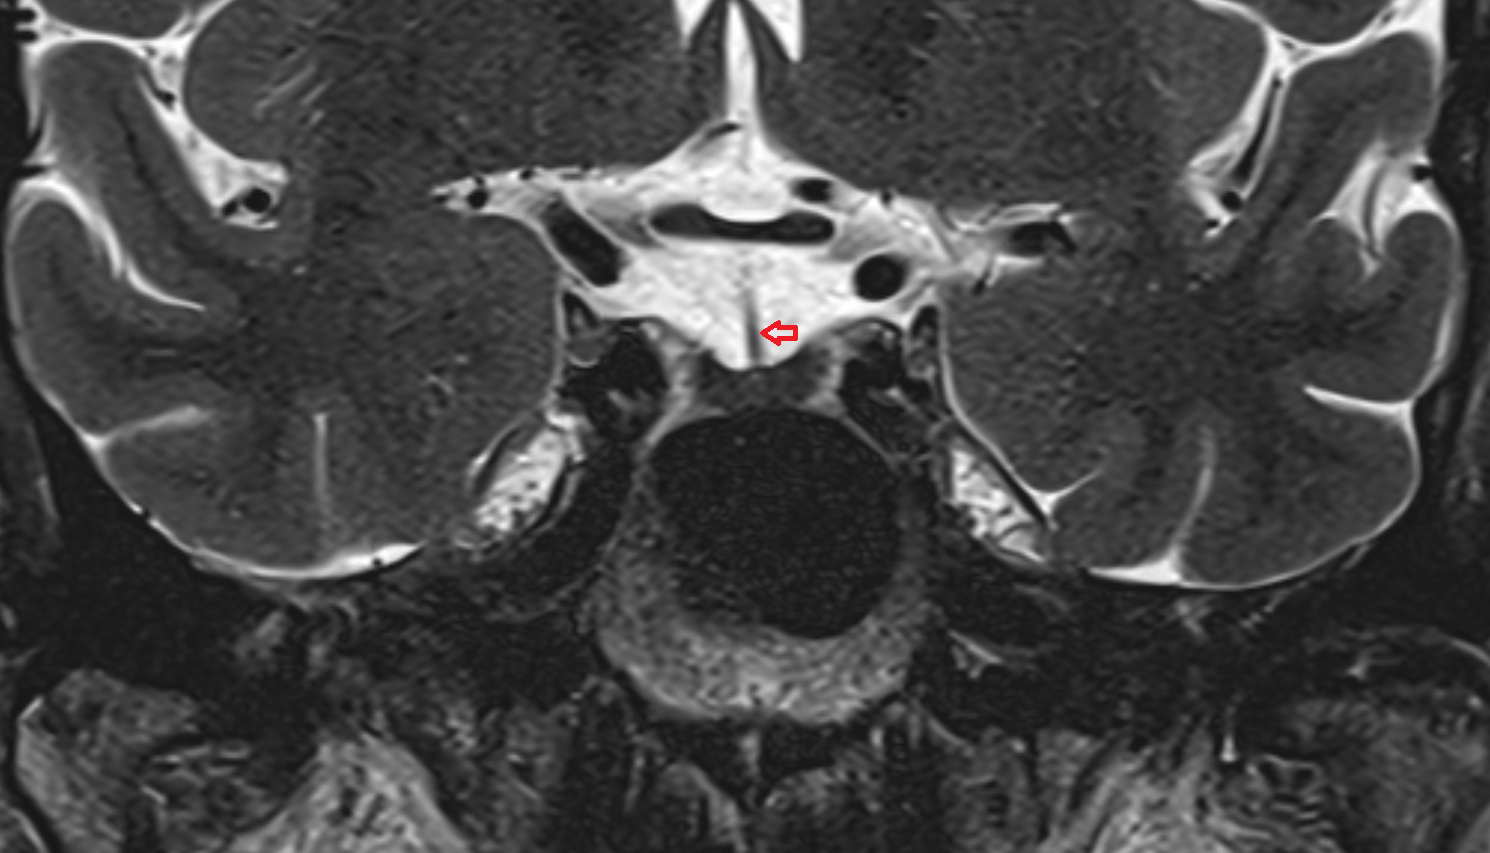

- Lateral aperture of fourth ventricle (foramen of Luschka)